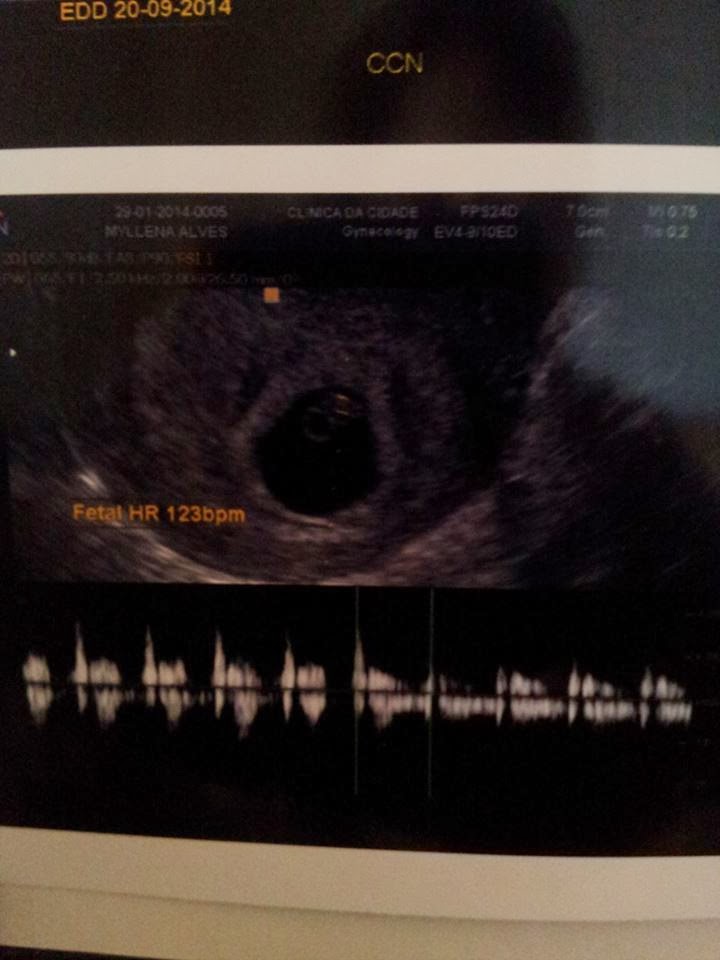

Momento único, inesquecível, maravilhoso e abençoado. Assim que a médica introduziu o aparelho lá estava ele(a), nem precisou procurar muito. Ahh minha gente podem dizer que é apenas um borrão pra mim não é (rsrsrs), já é o ser mais lindo, o filho mais amado. Ouvi o coraçãozinho, não chorei só sabia dar risada e olhar pra cara do Papai que foi junto pela primeira vez.

"Filho(a) és o presente mais precioso, uma benção de Deus. Por dias fiquei com medo de você não estar aqui dentro de mim, medo de ser algo da cabeça, mas foi um medo tolo bobo porque Deus é maior e esta fazendo tudo na melhor hora que é a DELE. Te ver ali com apenas 7,3mm e com 123 bpm me fez tão especial, tão feliz carregando o milagre da vida em meu ventre. Já te amamos tanto tanto tanto."

Pela DUM hoje estaria de 6 semanas e 6 dias e pela ultra deu diferença de 2 dias, estamos de 6 semanas e 4 dias. Esta tudo lindo aqui dentro e vamos que vamos cada dia mais amando esse momento.